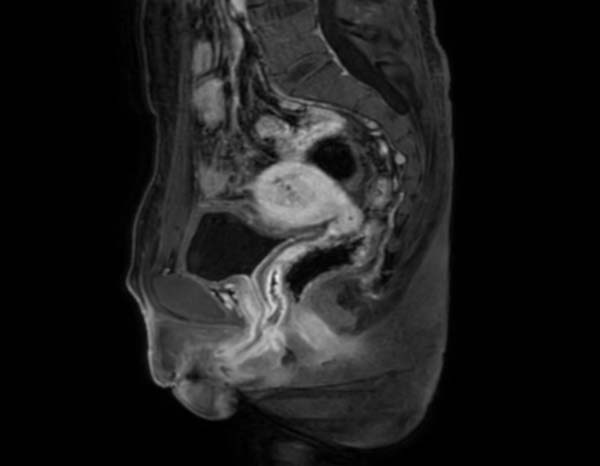

陳立得知真相後完全無法接受,因此向醫生強烈要求將自己的女性生殖器官切除,並繼續維持男性身份。負責手術的廣東婦幼保健院主任羅喜平表示,患者的子宮大部分位於腹膜外,小部分位於腹膜內,女性生殖器官解剖位置變異複雜,故手術難度相當大。

羅醫生又指,陳立體內的雄性激素偏低,而雌激素水平和卵巢功能與正常女性相當,屬於「真兩性畸形」,是一種極為罕見的病症。雖然對身體健康影響不算大,但對患者的心理影響則較多,例如有自卑感和尷尬感等。